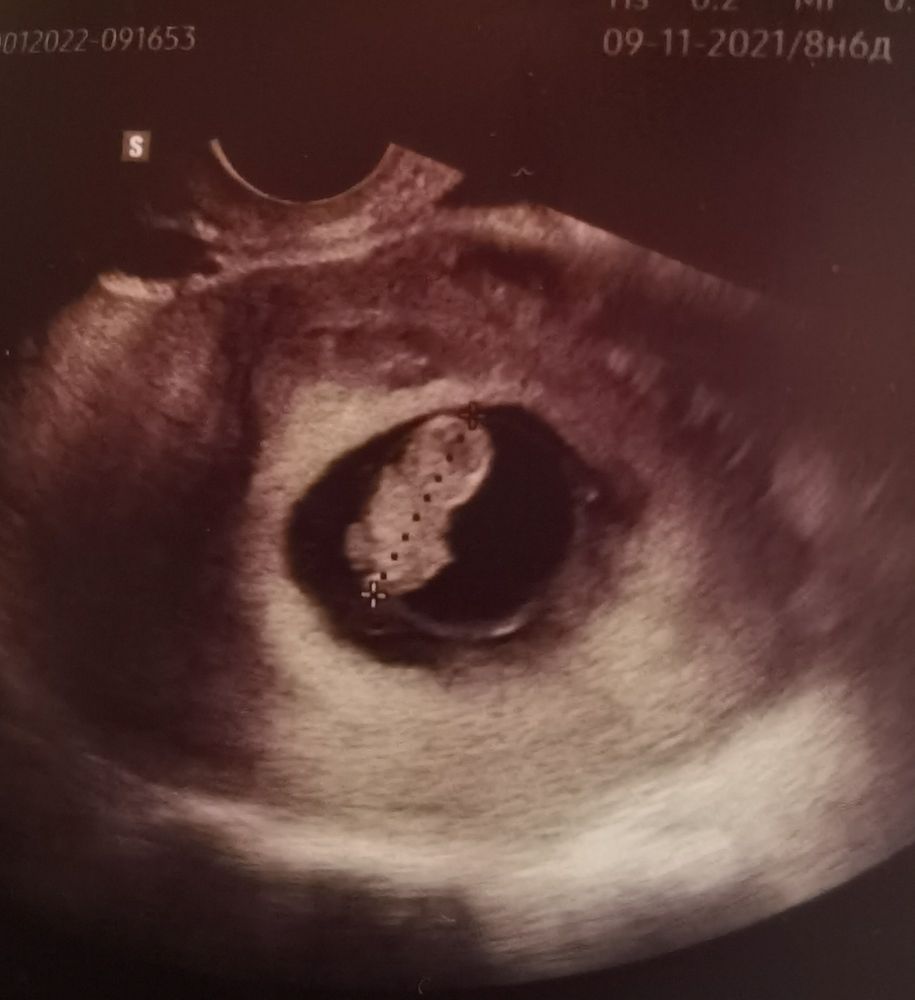

Где хореон?

Barbie Girl, ну хорион уже по УЗИ на таком сроке выглядеть сложно

Аня Жеребьёва, я в курсе. Но хорион уже на таком сроке найти затруднительно , он преобразовывается.

Аня Жеребьёва, я тоже читала. И сделала вывод, что по методу Рамзи , например , определение пола ребёнка по хориону такая возможность припадает только до восьмой недели , дальше уже определить его местонахождение по картинке УЗИ невозможно )

Ма Мышуля, какая плацента?🤣 Хорион там

Какое красивое фото💕 Ниточка идет к плаценте👍

Вот вы ребус загадали😃 а вам заключении не написали по какой стенке прикрепление?

Аня Жеребьёва, написали по задней. Хотела по методу Рамзи пол погадать 😆

Barbie Girl, ниче себе))) ну значит ниточка ведёт к задней стенке)